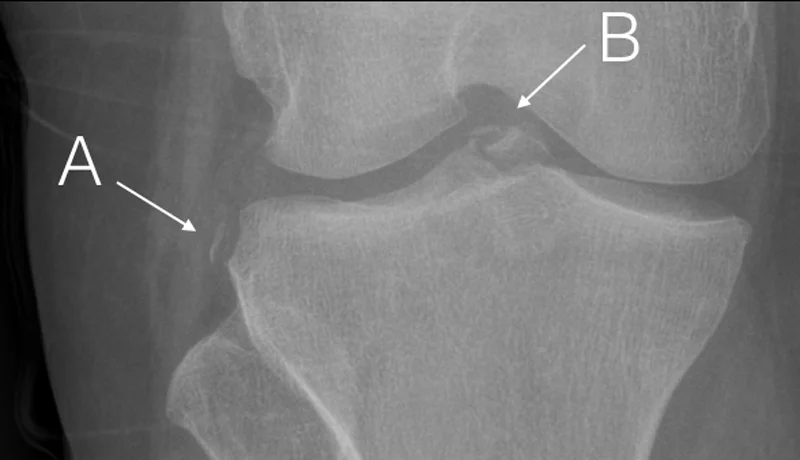

Final Diagnosis: Segond fracture with ACL disruption

Case Conclusion:  An elliptic fragment of bone is seeing parallel to the tibia and just lateral to the tibial plateau (A).  This avulsion fracture is recognized as a “Segond fracture”, which is classically associated with an ACL tear.   To further support this, the patient also has an avulsion fracture of the intercondylar eminence where the ACL inserts (B).

The Segond Fracture is one such example [1,2,3].  The typical mechanism is internal rotation of the knee with varus stress. This small cortical avulsion may only be appreciated in the AP-view of the knee.  While it is an avulsion fracture of the anterolateral ligament of the knee (ALL), an associated ACL tear is found in 75-100% cases.  As in the case of this patient, there may be an associated abnormality in the ACL donor site as well. The less common “Reverse Segond fracture” (ellipitical bone fragment arising from the medial aspect of the proximal tibia) is caused by external rotation with a valgus stress. It is associated with significant injury to the PCL as well as tears of the medial meniscus.  In general, these are both considered fractures of the tibial plateau and are managed with a long leg cast and orthopedic referral.